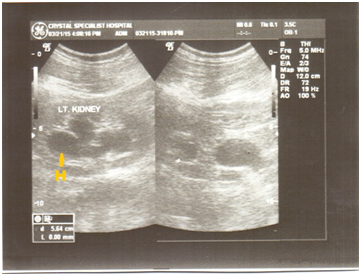

Sonographic confirmation of hypertrophied but ‘polar’ kidneys; similar to embedded renal cysts with predominantly low echogenicity and multiple sonopenic fluid spaces (Figure 1&2). A General Electric (GE) Pro-Logic 3 ultrasound machine (made in the USA) with a 3.5 MHz curvilinear transducer was used for scanning. There was no sonic evidence of malignant disease. Informed consent of patient was obtained and ethical approval was granted by CSH in line with the 1975 reviewed Helsinki Declaration on confidentiality and patient-rights. Prior to the diagnosis of hydronephrosis, fasting for 6 hours and dehydration test was made. Recent history review through oral discussion with patient and medical case-note revealed compulsive and excessive water intake about 5 years ago (Table 1).

Figure 2 (Ultrasound B-mode split image) RT kidney with possibility of refluxing primary mega-ureter. Progressive renal failure can occur even after treatment due to abnormal physiologic bladder function. Note the arrow pointed downwards.

By July 2016 (see sonograms), no reflux in patient was observed post-micturition cystography. At present, December 2016, after follow-up presentation for ultrasound, increased urination averaging 29 times/day, with stable kidney function; serum creatinine: 1.48 mg/δl. Though some patients have undergone surgical procedure to alleviate functional obstruction,8 it is advisable treatment is medical. Instruction to patients on the importance of early frequent voiding cannot be overemphasized. The RT kidney (Figure 1) measured 118 x 62mm in longitudinal and AP diameters, LT kidney (Figure 3&4) dimension was 120 x 65mm before progression.